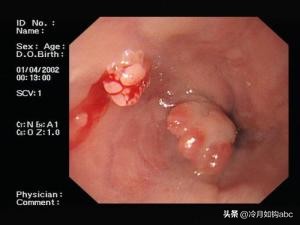

食管壁息肉胃镜下图像,出血为活检所致